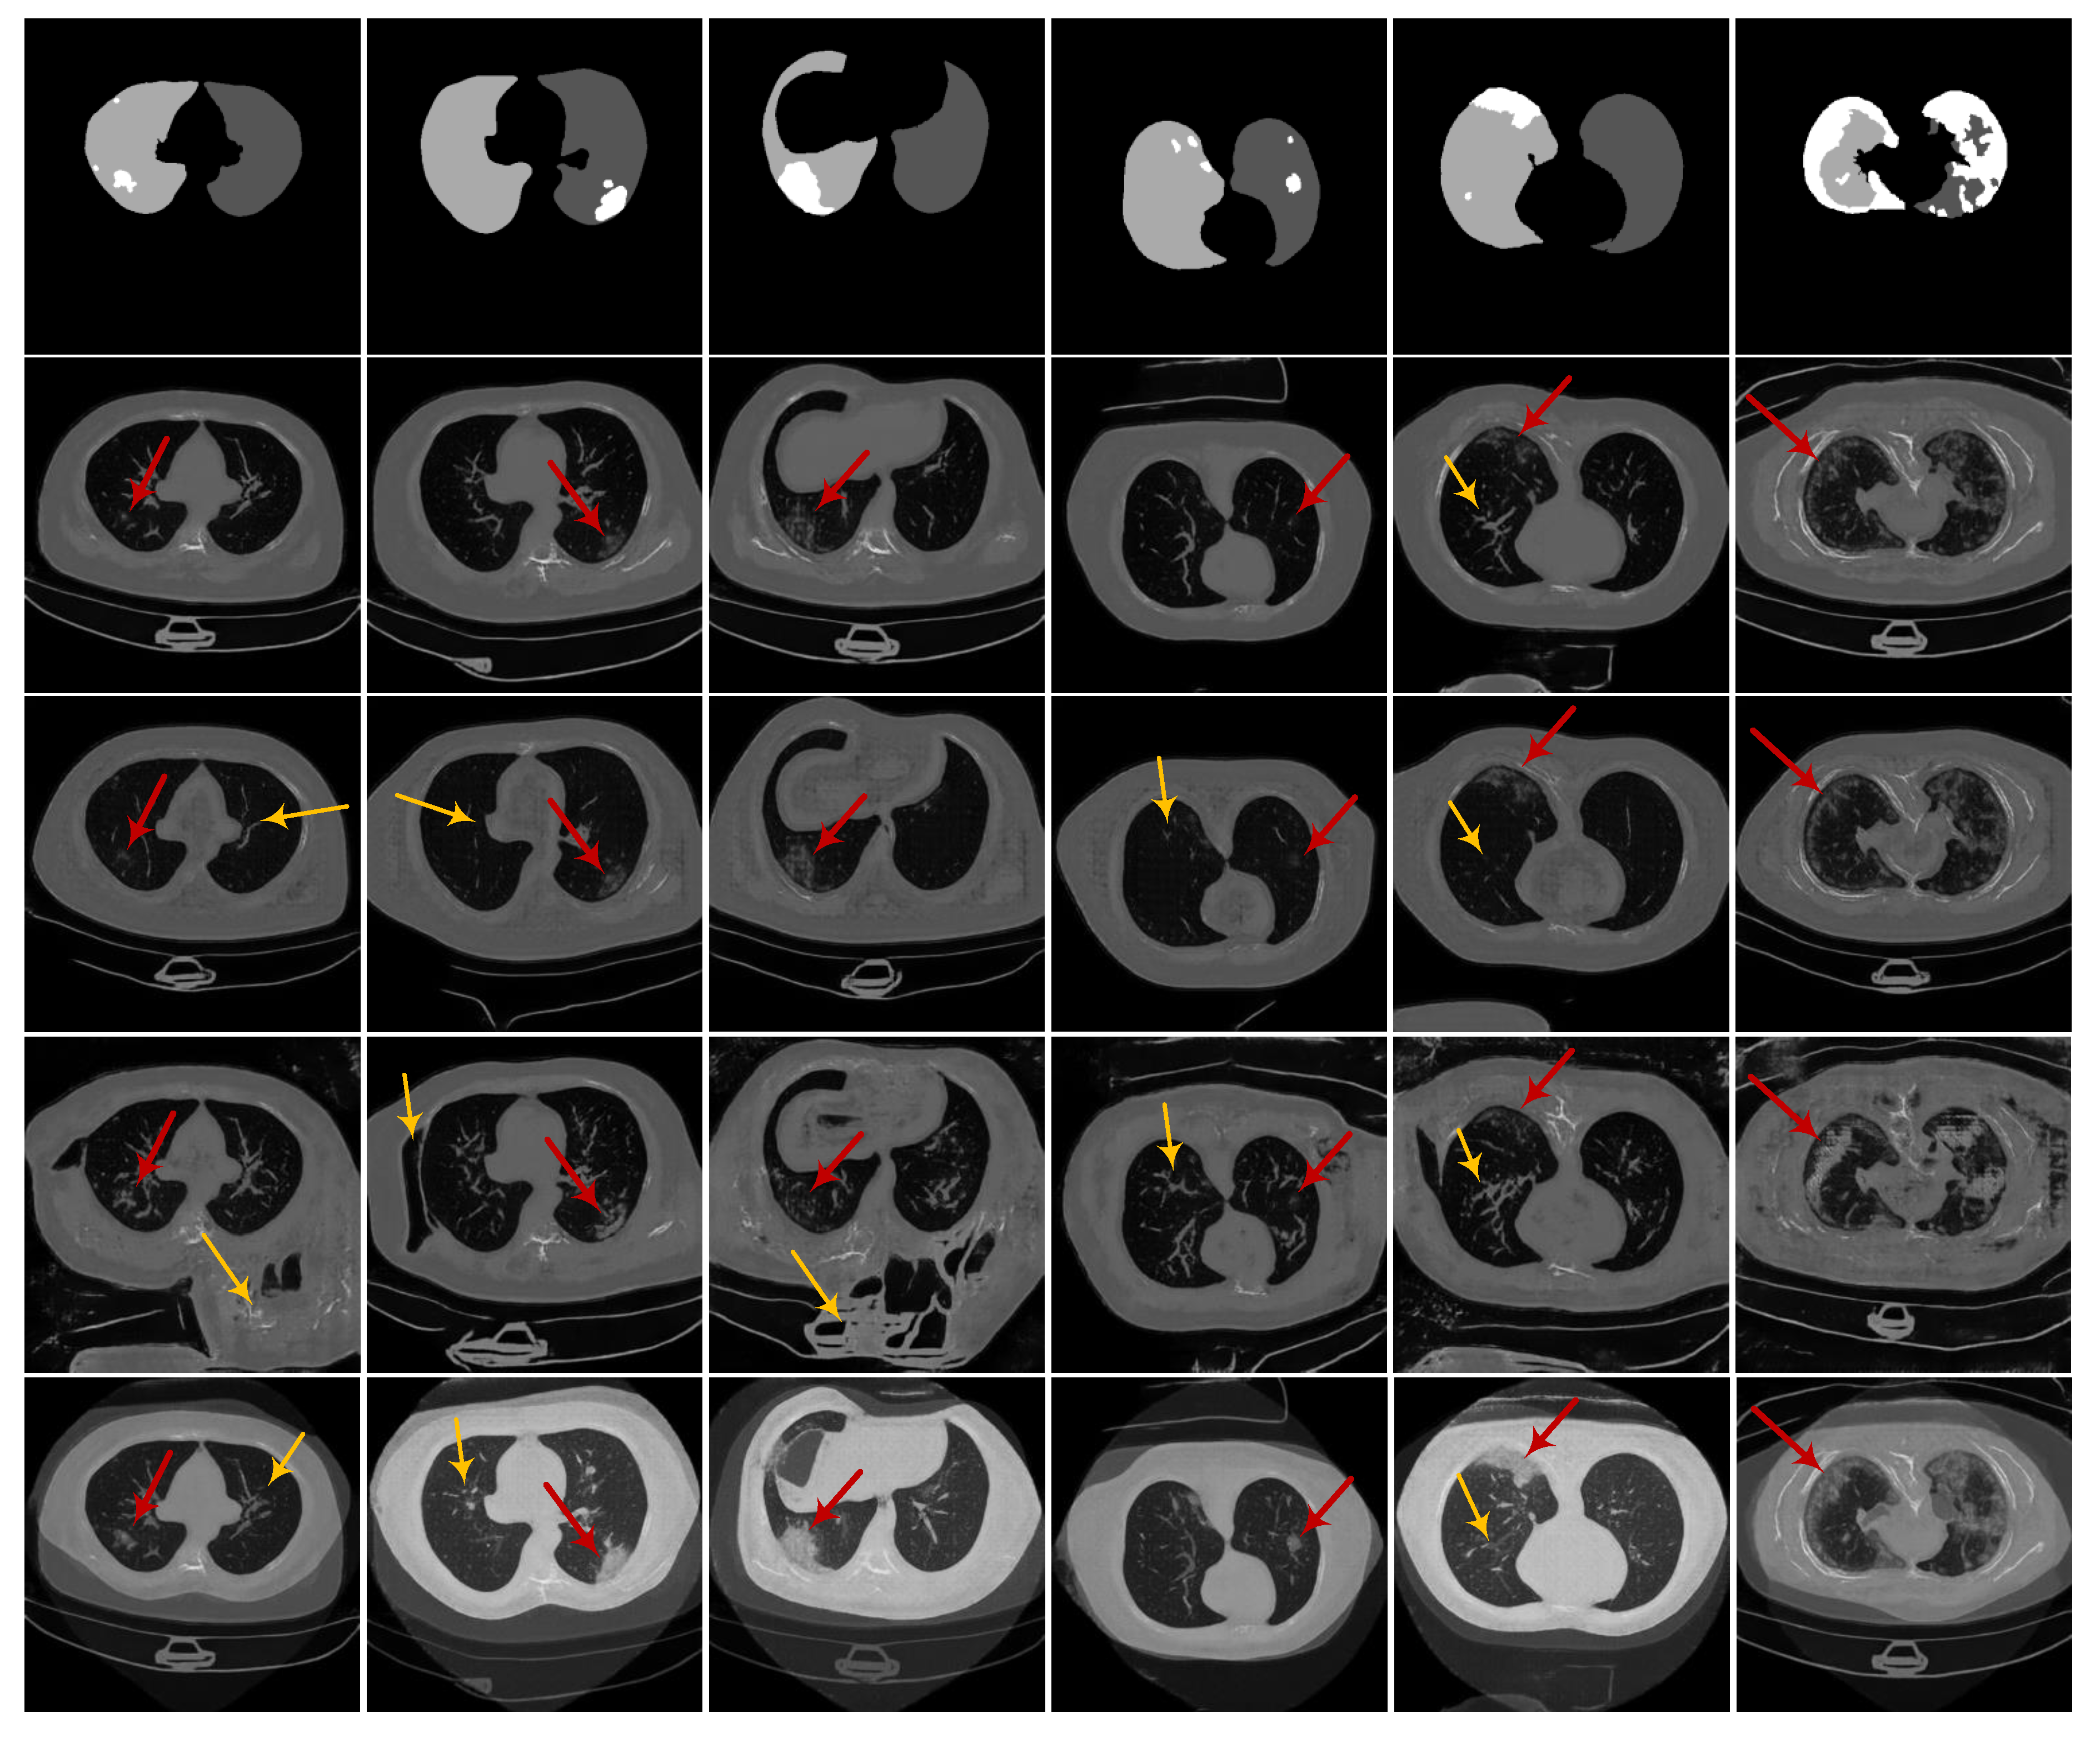

3.1. Experiments on Synthesizing Radiological Images

3.1.2. Ablation Experiments

3.1.4. Evaluation on the Ability of CoSinGAN in Generating Diverse Samples